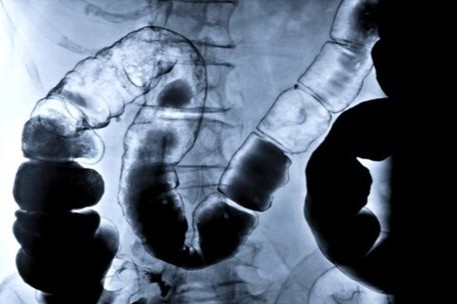

| Thụt rửa đại tràng thực tế là một phương pháp y khoa được áp dụng trong những trường hợp bệnh lý. Ảnh: FactDr. |